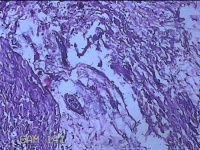

左侧腋下结节

性别

女

年龄

22岁

临床诊断

皮下结节;皮脂腺囊肿

一般病史

发现左侧腋下结节伴隐痛不适1周余。

标本名称

大体所见

灰白暗红色带皮肤样结节2.5x1.5x0.7cm一个,表面糜烂,切开结节呈实性,切面灰白淡黄色,质软。

图1